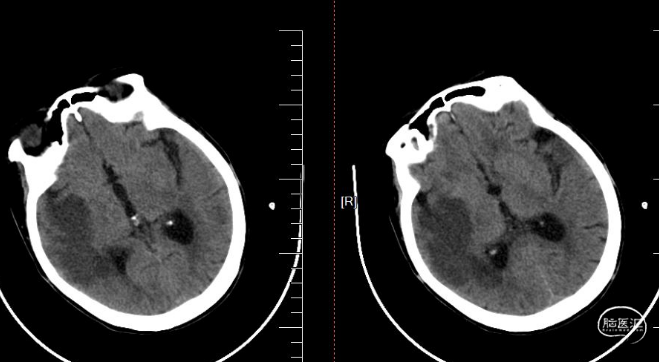

术前影像

术前CT, Aspects评分5分